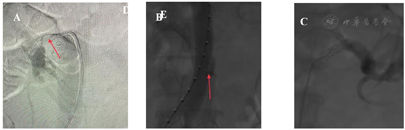

患者,男,49岁,"血压升高十余年,血压控制不佳8个月"。患者10年前发现血压升高(具体诊治不详),最高血压230/120 mmHg,平素服用"拜新同30mg qd、厄贝沙坦75 mg Bid、美托洛尔12.5 mg Bid"血压控制于130/80 mmHg。8个月前血压控制不佳,血压最高190/120 mmHg就诊于我院门诊。双肾超声提示:"右肾动脉狭窄,右肾体积略缩小(9.8 cm×4.6 cm)",收治我院泌尿外科,于2020-8-31行双肾动脉选择性造影:右肾动脉开口90%狭窄(图1A),左肾动脉近段80%狭窄(图1B),分次左、右肾动脉植入支架,术后造影双肾动血流通畅,无明显残余狭窄(图1C)。住院期间未进行大动脉炎(TA)筛查,术后患者服用"拜新同30 mg Bid、美托洛尔25 mg Bid、阿司匹林100 mg qd",血压降至130/80 mmHg。2021年4月初(肾动脉支架植入术后8个月)血压再次升高至200/120~130 mmHg,自行调整"厄贝沙坦150 mg Bid"血压仍无明显下降,门诊收入心内科。